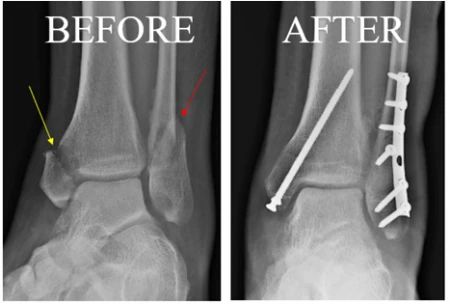

Ankle Breaks - The same mechanism of injury, or traumatic event, which can cause an ankle sprain can also result in a broken bone. Depending on the location and severity of the fracture, sometimes they can be treated non-surgically with immobilization in a cast or walking boot. Other times, a surgery called an Open Reduction Internal Fixation (ORIF) is needed to repair the broken bone. Broken down, this procedure involves opening up the skin with a surgical incision, placing the broken pieces of bone back together, and securing them with plates and screws to maintain their position. The pictures below can be found at the American Orthopaedic Foot and Ankle Society site here. They show the before and after of an ORIF. The yellow arrow is pointing to the medial malleolus of the tibia, while the red arrow is pointing to the lateral malleolus of the fibula. You can see the plates and screws used in the after image that are holding the fracture pieces together!